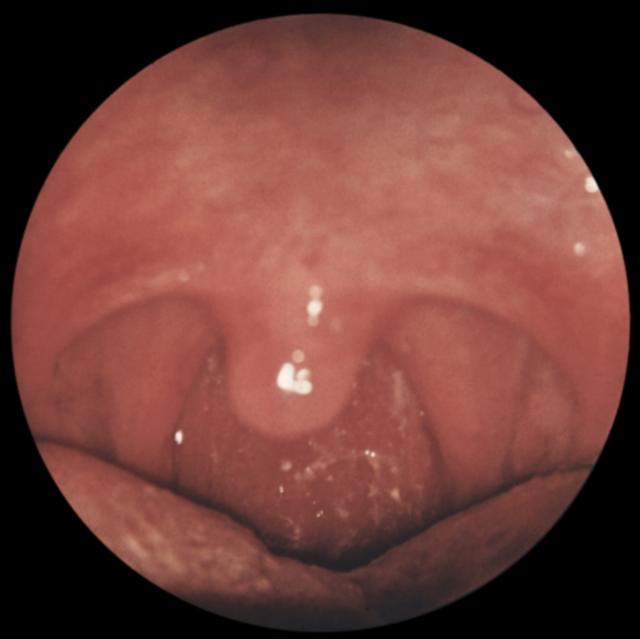

Рис. е). Вид зева при хроническом катаральном фарингите.